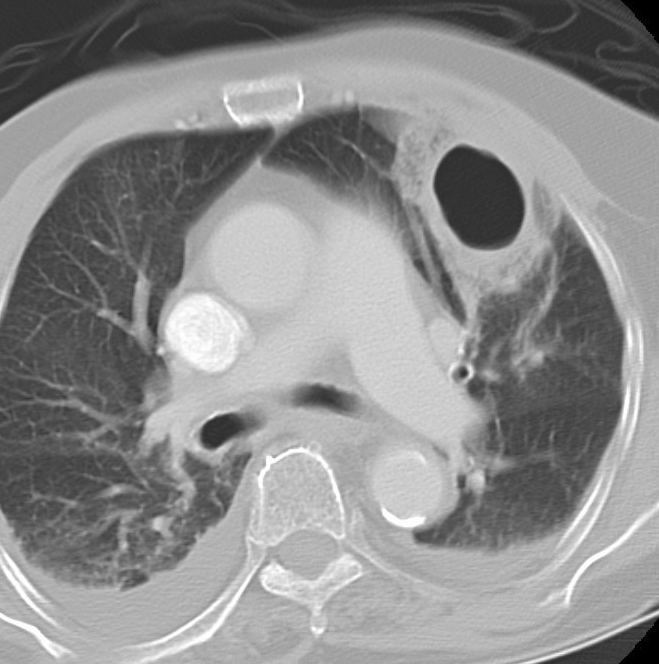

Abscess CT